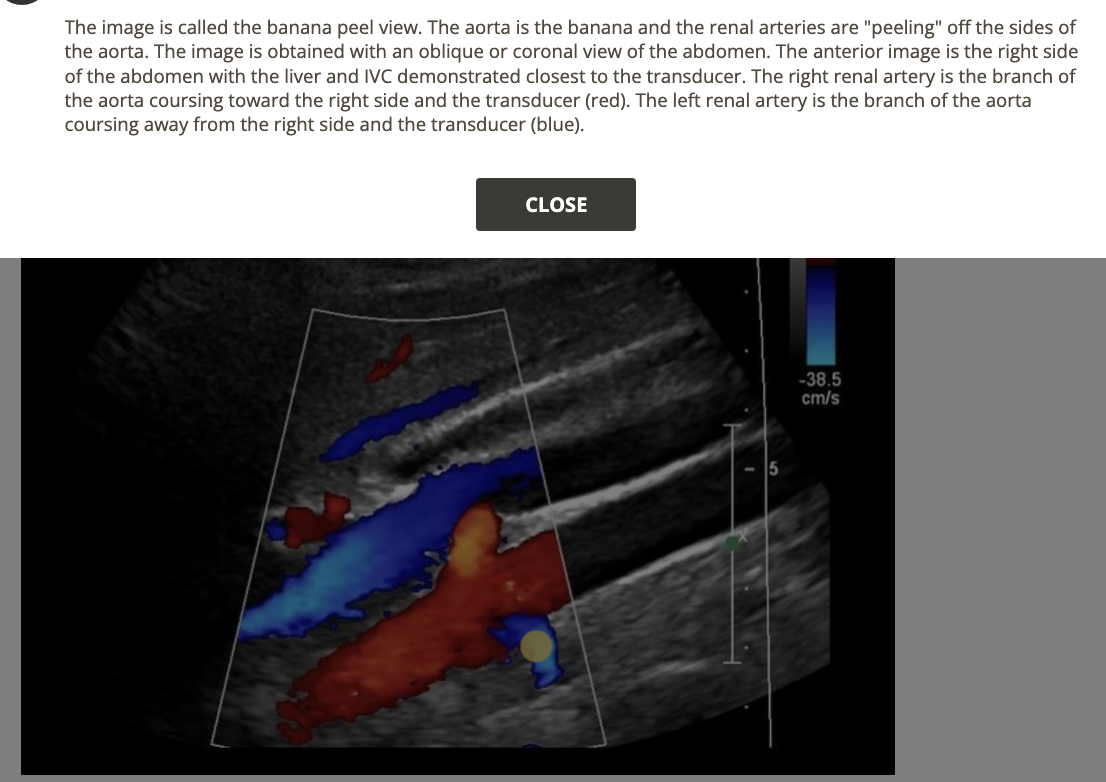

![<p>where is the superior mesenteric artery [SMA]</p><p>.</p><p>write [anterior to left renal vein]</p>](https://knowt-user-attachments.s3.amazonaws.com/a0ad8e36-963b-464b-809a-668896716acd.png)

where is the superior mesenteric artery [SMA]

.

write [anterior to left renal vein]

anterior to left renal vein